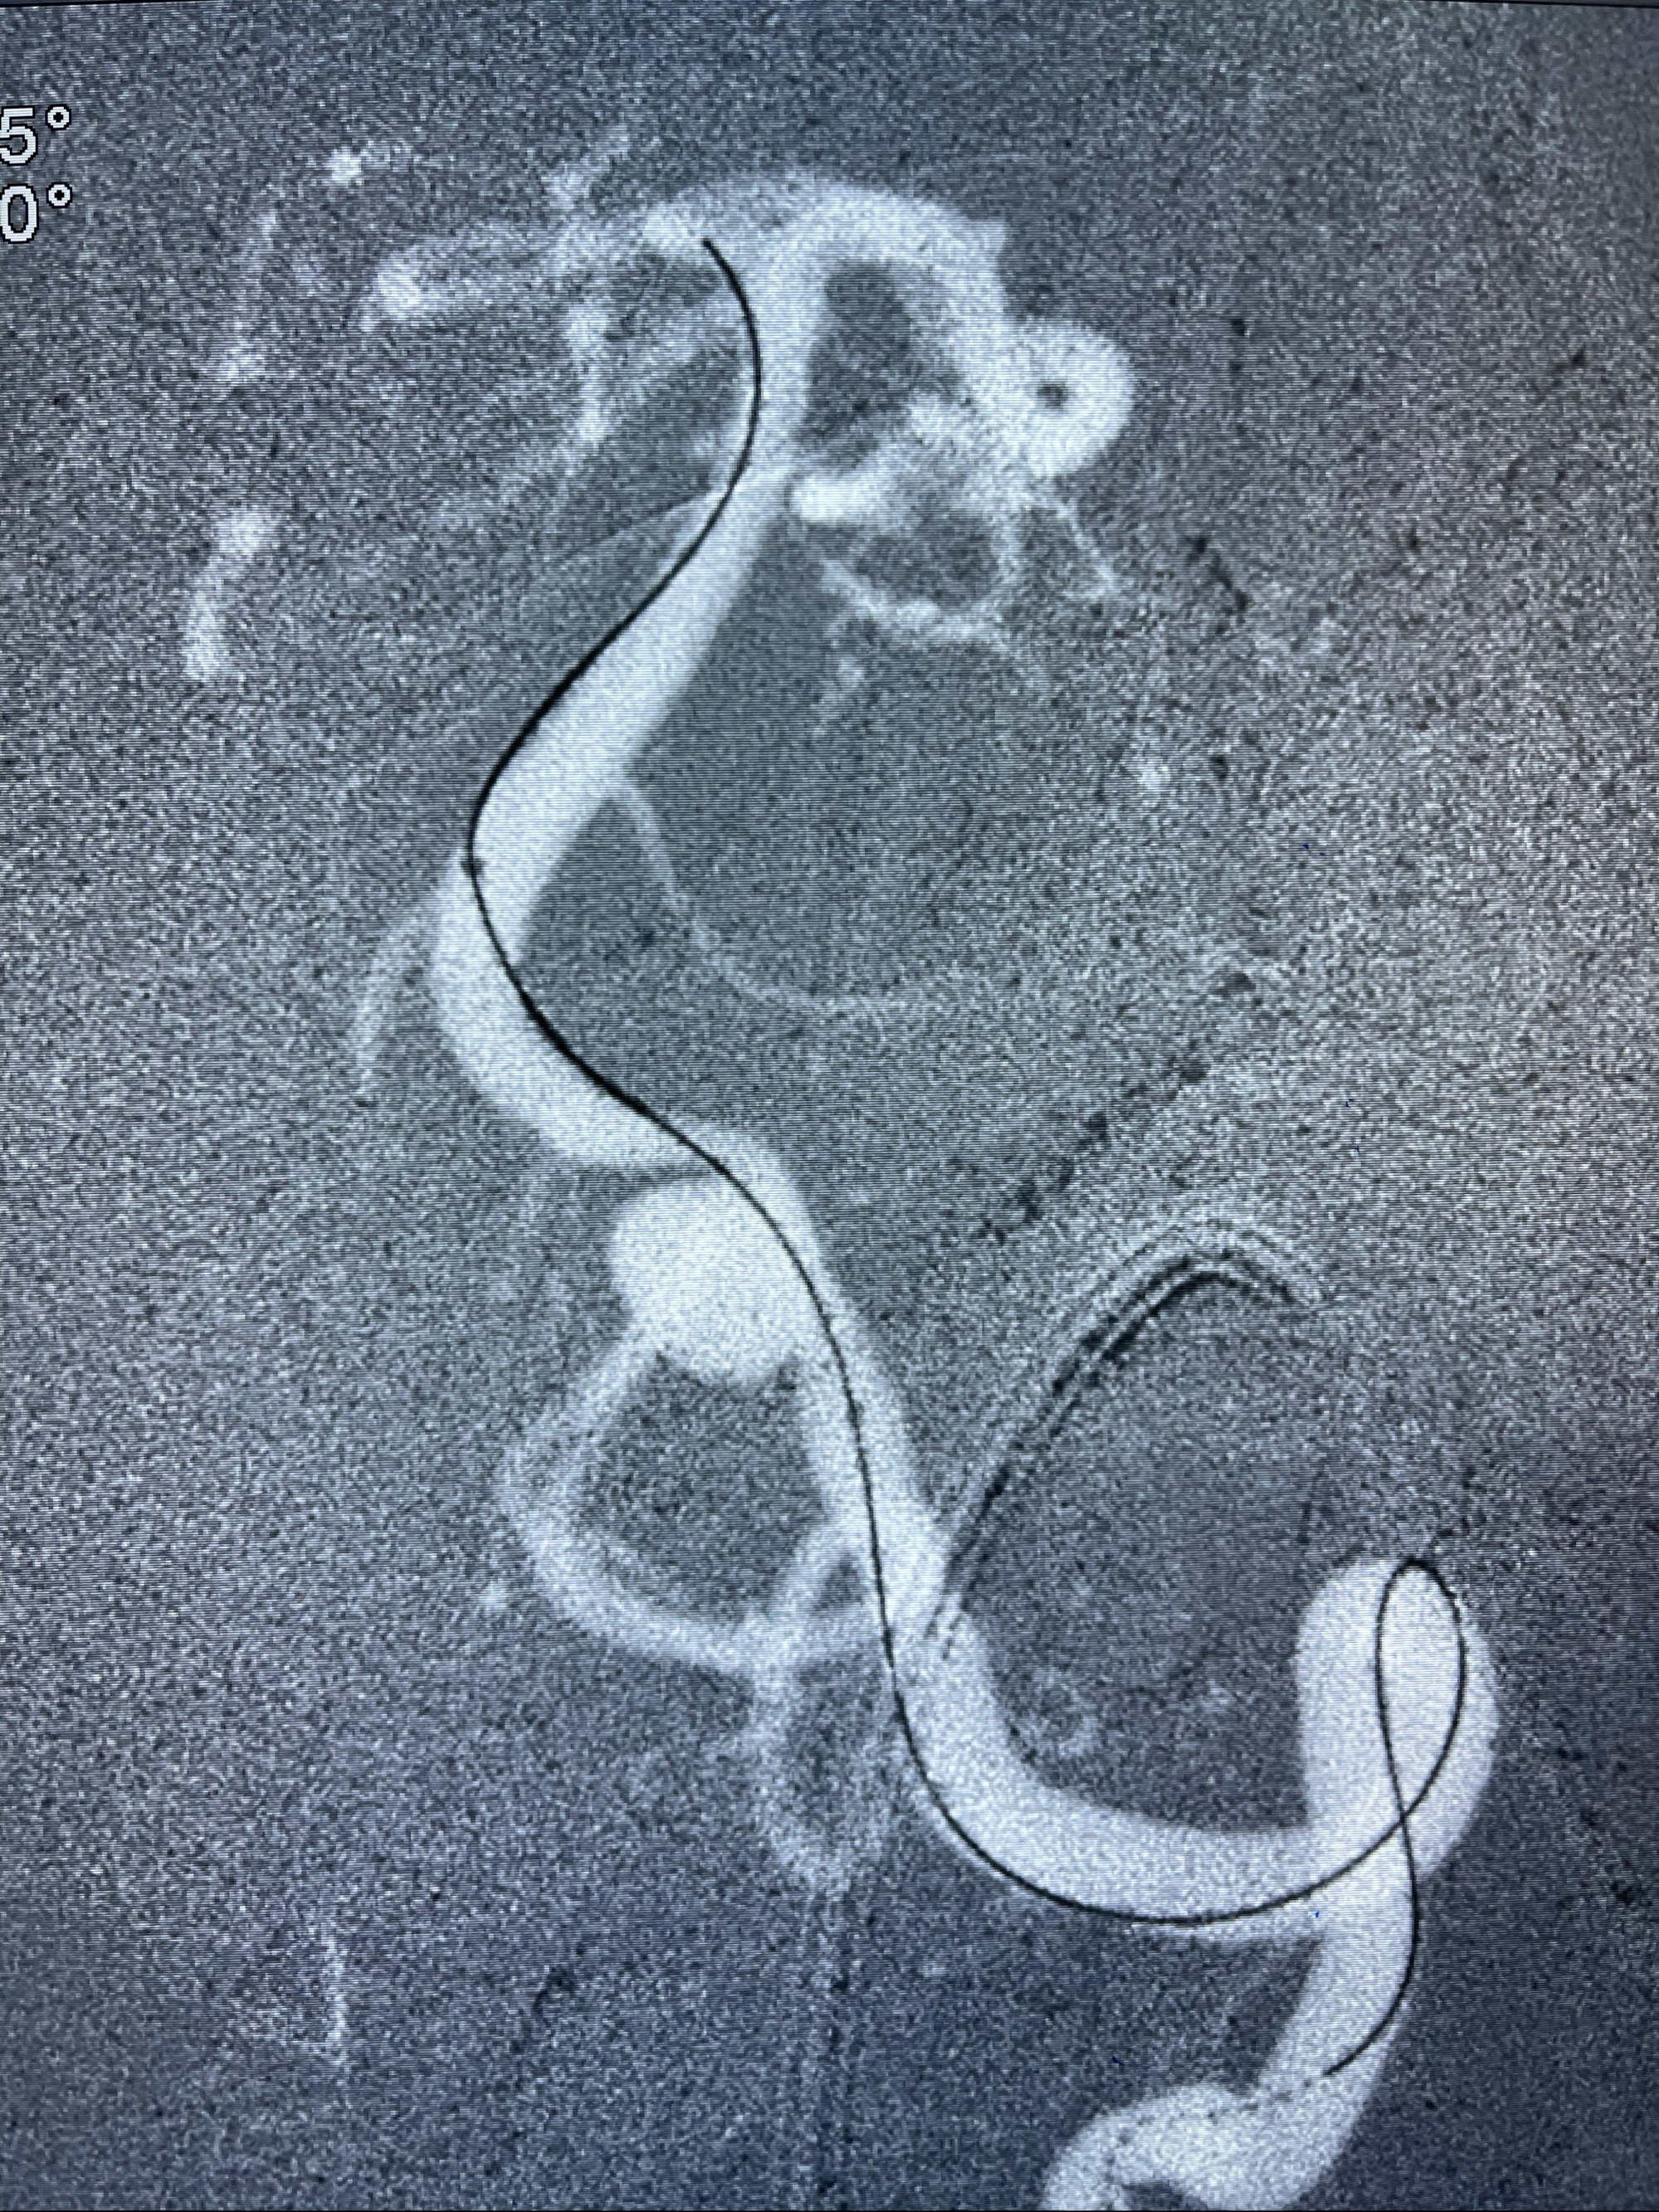

工作角度造影

Eterprise4.0-23mm支架导管到位

Echelon10 45°角微导管塑形后到位

8mm-40cm微弹簧圈成篮

即刻造影